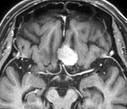

ところが、たとえ腫瘍が小さくても、下の画像に示すように、造影される病変(左)に比べ、脳浮腫(右;白く広がっている部分)が広い範囲に拡大していると、腫瘍の大きさが小さいにも関わらず症状(この場合右足の麻痺やてんかん発作)が重症化することが多いです。腫瘍摘出を行なうと、術後3~4週間で浮腫は消失します。

(術前MRI)